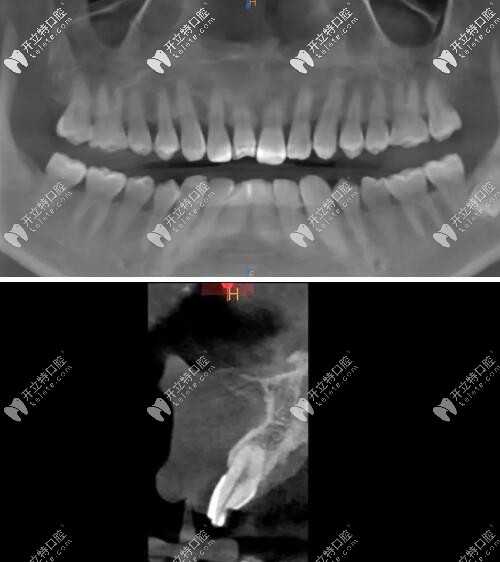

影像學(xué)檢查

門牙磕斷傷及牙根影像學(xué)檢查

被磕的牙冠根向折裂,直達(dá)骨下;

牙根骨量充足;

牙長軸和牙槽骨的方向基本一致。